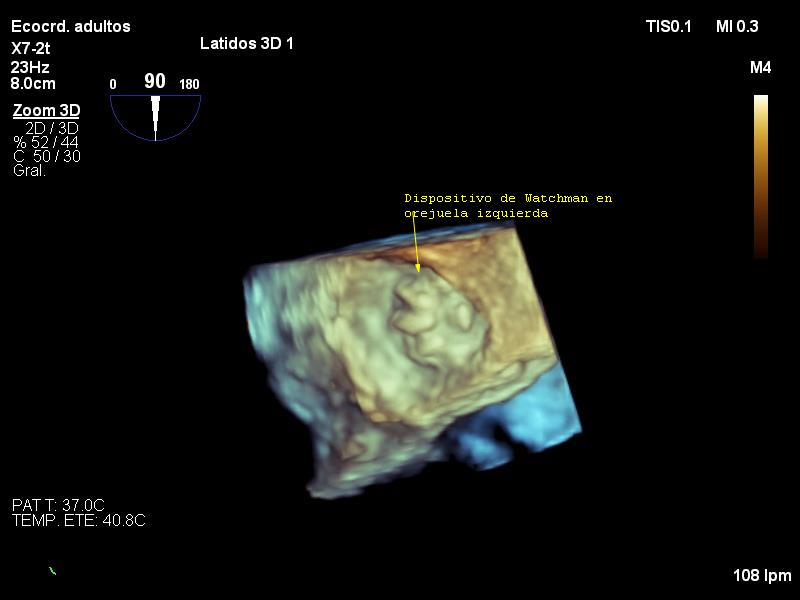

A pesar que la fibrilación auricular no valvular (FANV) es una de las enfermedades más frecuente en nuestra sociedad su prevalencia va a aumentar en los próximos años por el envejecimiento progresivo de la población. El cierre percutáneo de la orejuela izquierda constituye una alternativa para enfermos con FANV y contraindicación al tratamiento con anticoagulante. El cierre de orejuela es un procedimiento seguro y eficaz. El cierre de OI podría ser en el futuro una alternativa al tratamiento con anticoagulantes orales (ACO) para todos los pacientes con FANV. Presentamos un paciente con contraindicación a los ACO a la cual se le implantó un dispositivo de cierre Watchman con una evolución favorable a los cuatros años del procedimiento.